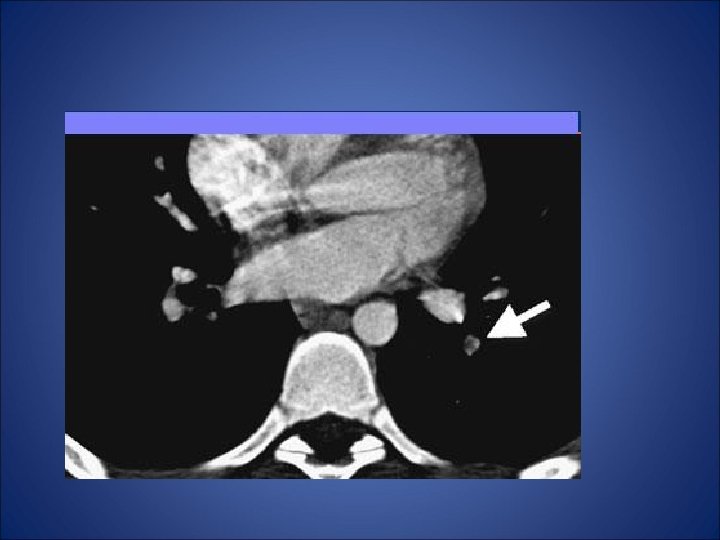

Embolism pulmonar acut • - desi simptomele clinice indica embolismul pulmonar (durere pleuritica, dispnee), pacientul din cazul de fata nu prezinta niciun factor de risc (chiar mai mult ca factori de preventie avem varsta si activitatea fizica) - pentru certitudine s-a folosit investigatia CT care a relevat multipli emboli atat in vascularizatia majora a plamanului stang cat si a celui drept - orice evaluarea ulterioara a pacientului nu a putut elucida cauza embolismului. • Nu exista suficiente referiri la naproxen in cazurile raportate de embolism pulmonar si astfel nu poate fi incriminat pentru producerea acestui fenomen. Mai mult, dupa tratamentul intraspitalicesc pacientul a refuzat tratamentul cu warfarina si la la cateva luni au aparut alte episoade de embolism. Decizia terapeutica finala a fost plasarea unui filtru Greenfield de vena cava inferioara.

TC abdominal